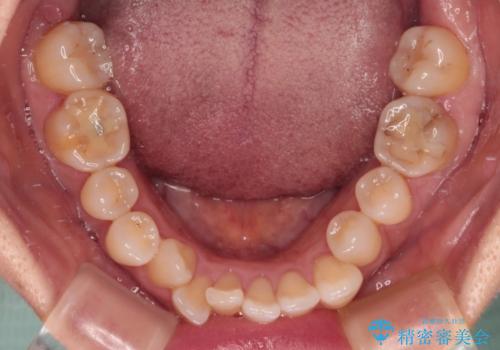

- 前歯のデコボコと咬み合わせの悪さを気にして来院された患者様です。

下顎骨が左側にズレて成長してしまったため、左側の咬み合わせが上下反対になっている状態でした。